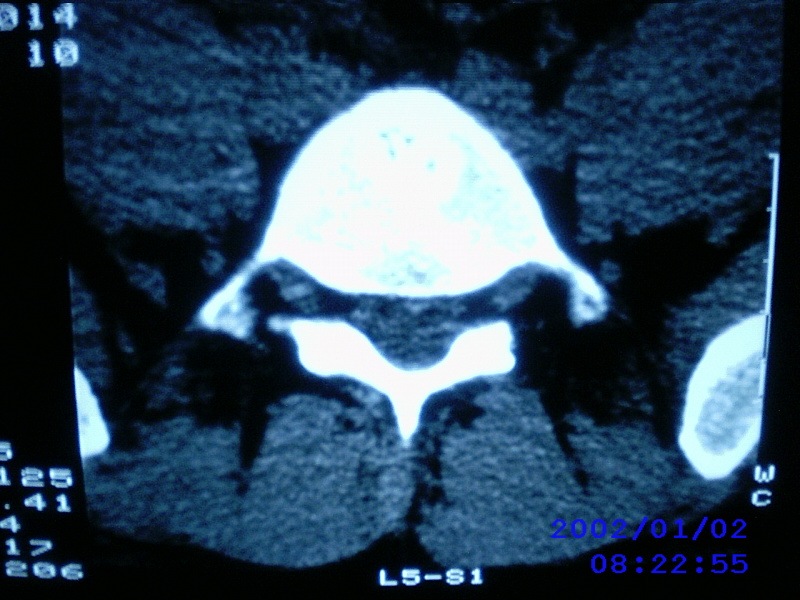

患者,男性,40岁,腰痛伴左下肢疼痛、麻木6年。5年前做过腰椎间盘手术,具体是哪个位置病人记不清了。

我拍的是l4-5、l5-s1

l5/s1术后

l4-5/l5-s1都做过。又有突出了

1)l4/5及l5/s1左侧椎板术后改变。2)l5/s1椎间盘突出,l5椎体下缘许莫氏结节。3)l4/5椎间盘膨出并突出。4)l3/4椎间盘膨出。

1)l4/5及l5/s1左侧椎板术后改变。2)l5/s1椎间盘突出,l5椎体下缘许莫氏结节。3)l4/5椎间盘膨出并突出。

1)l4/5及l5/s1左侧椎板术后改变。2)l5/s1椎间盘突出,l5椎体下缘许莫氏结节。3)l4/5椎间盘膨出并突出。4)l3/4椎间盘膨出。支持!